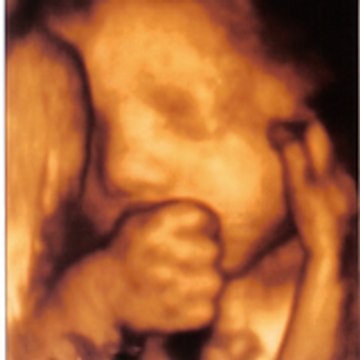

Orlane 36 SA

239 views · 18y ago 🎲 Random